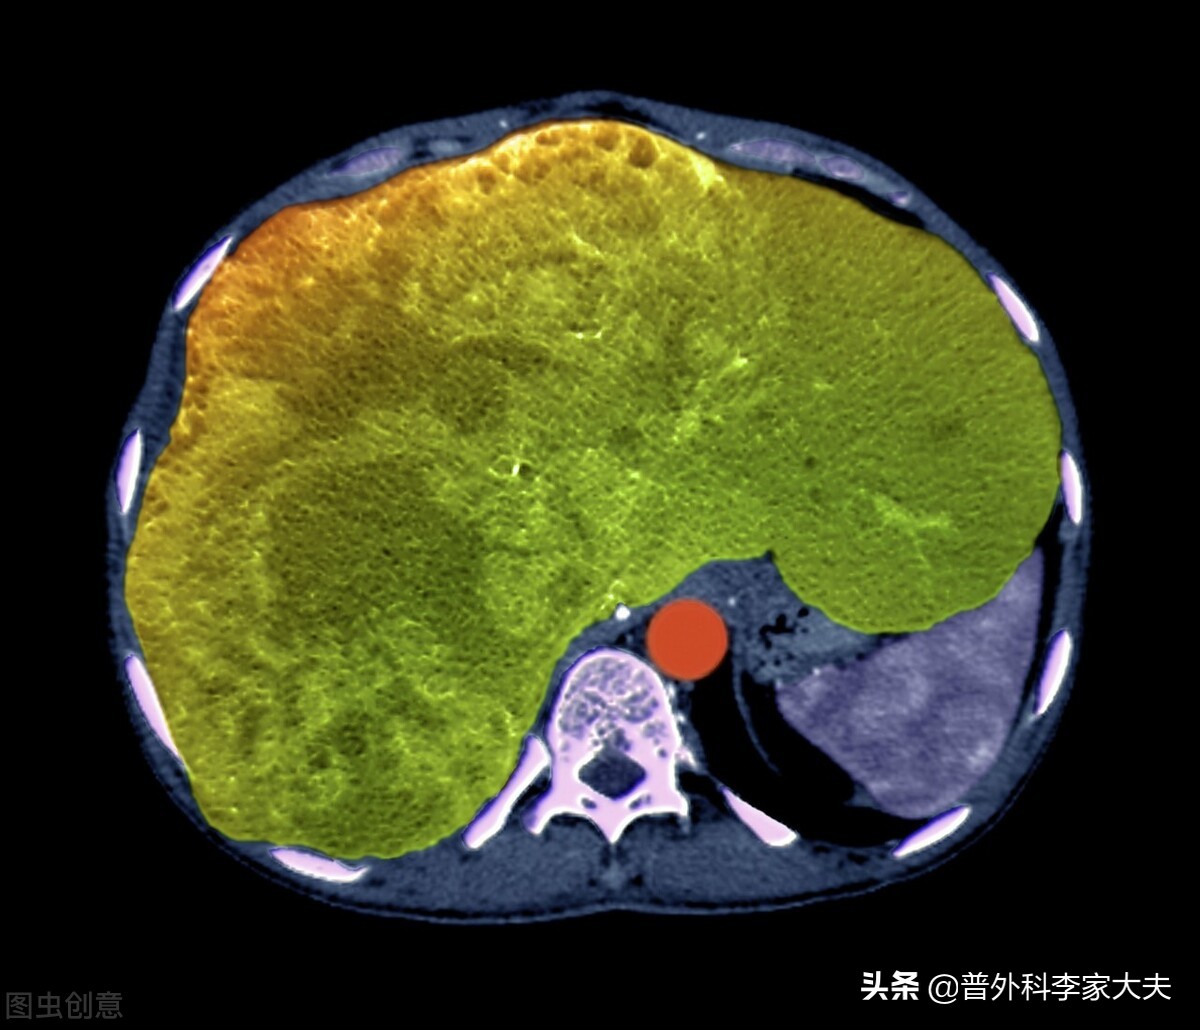

肝癌患者

从减少肝癌并发症的角度考虑:

肝癌晚期患者,多数是在肝硬化病变基础上进展而来,而肝癌进展到晚期后,又往往加重患者肝硬化病变,导致不少病人出现门静脉高压症病变,不少肝癌晚期患者,因此存在食管胃底静脉曲张与门静脉高压性胃病情况。因此,不宜进食粗糙的食物,以免造成上消化道大出血。另外,多数晚期肝癌患者,常合并有凝血功能障碍、贫血与低蛋白血症情况。因此,从减缓肝癌晚期患者贫血,患者宜进食新鲜干净的蔬菜水果,补充维生素B与叶酸等,有利于纠下患者贫血情况。与此同时,也要注意增加适合患者身体的蛋白质丰富食物的进食。